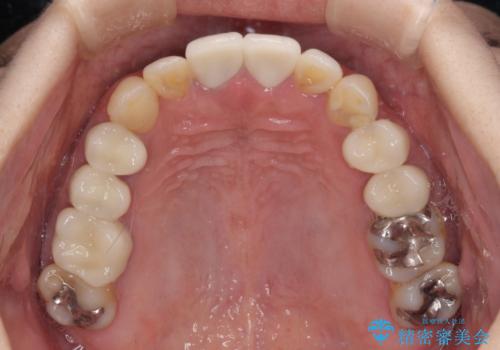

- 右下の欠損部の治療を希望して来院された患者様です。

部分矯正を行った後にインプラント埋入と手前の歯の根管治療を行い、その後補綴治療を行うこととしました。

治療途中より、上の歯や反対側の銀歯、上顎前歯の色合いや下顎前歯のデコボコが気になってきたため、全てを治療することとしました。